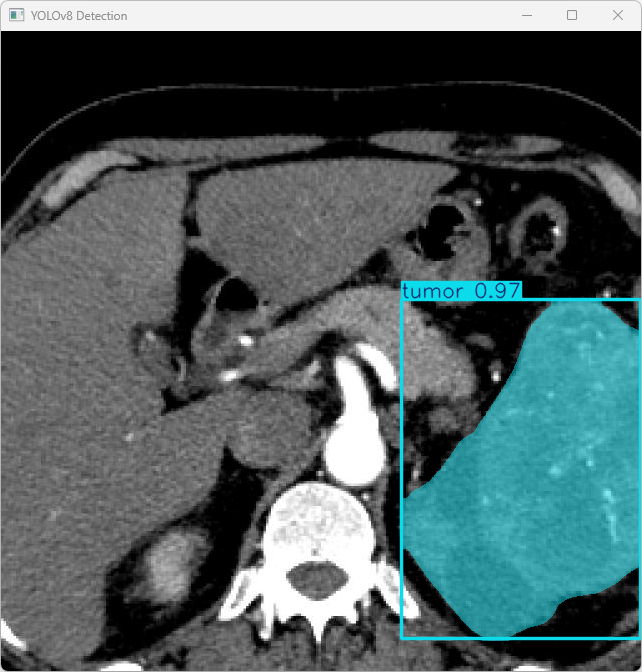

执行imgTest.py代码后,会将执行的结果直接标注在图片上,结果如下:

这段输出是基于YOLOv8模型对图片“benign (9).png”进行检测的结果,具体内容如下:

图像信息:

(1)处理的图像路径为:TestFiles/imagetest.jpg。

(2)图像尺寸为640×640像素。

检测结果:

(1)模型在图片中检测到:1 个肿瘤(tumor)。

处理速度:

(1)预处理时间: 4.5 毫秒

(2)推理时间: 27.1 毫秒

(3)后处理时间: 74.5 毫秒

总结:

YOLOv8模型成功检测到 1 个肿瘤,推理速度良好。